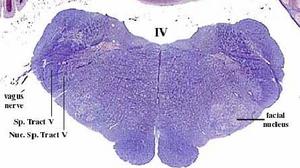

secciones transversales a diferentes niveles del tronco del encéfalo mostrando la localización de los núcleos neuronales aferentes de los nervios craneales

AFERENTES:

Somatoaferentes:

generales (GSA): boca y cara

-especiales (SSA): sentido de la visión y oído

Visceroaferentes:

- generales (GVA): recogen sensación de faringe y laringe

-especiales (SVA): sentido del gusto y del olfato